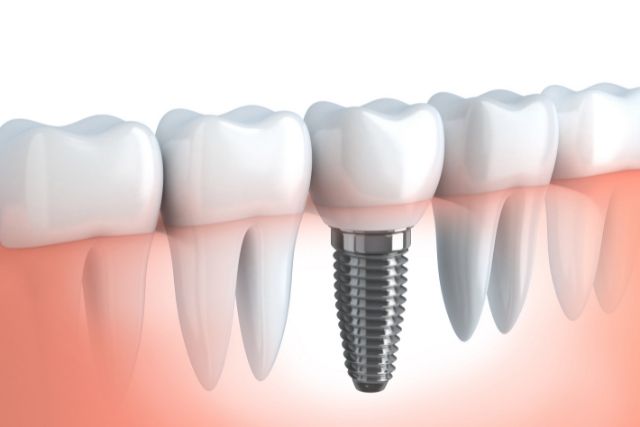

インプラントはあなたの顎の骨にドリルで穴を開け

ネジを埋め込み、骨とくっつけてしまうものです。

つまり、

インプラントは一度埋め込んだら動かない。

堅くくっついていますので、動かないのです。

建物を建てる時の

柱と思って下さい。

堅くて強い柱をドーンと顎の骨に埋め込んで

強く固定するのです。

しかし、

インプラント以外のあなたの歯は

簡単に動きます。

ご自身の歯は簡単に動くのです。

ご自身の歯は歯根膜というクッションによって覆われていますから

物と物を噛んだ時に一瞬当たった後、動いているのです。

歯は一生動き続けます。

インプラントを1本でもあなたの口の中に入れるということは

動き続けるご自分の歯と

まったく動かないインプラントとが

共存していく、ということを意味します。